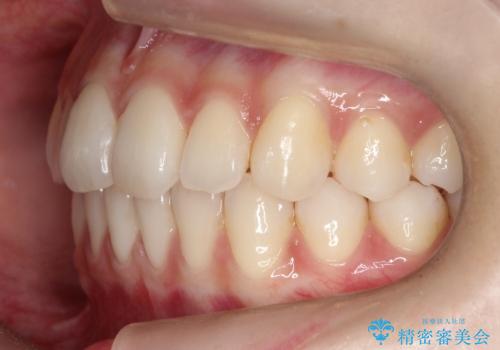

見た目、嚙み合わせ及び、治療期間や施術内容に大変ご満足いただきました。

- 前歯の見た目と噛み合わせの改善を希望され来院された患者様です。